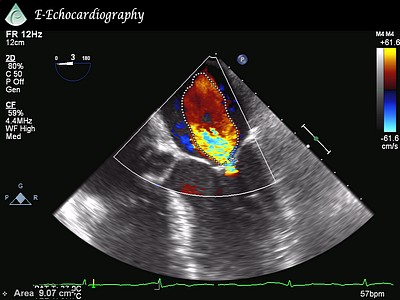

74 y.o. female with a history of SOB, DOE, and CHF.

What is the severity of the AS?

What is the severity of the MS?

Which MVA is correct (PHT or PISA) and why?

What is your recommendation for this patient?